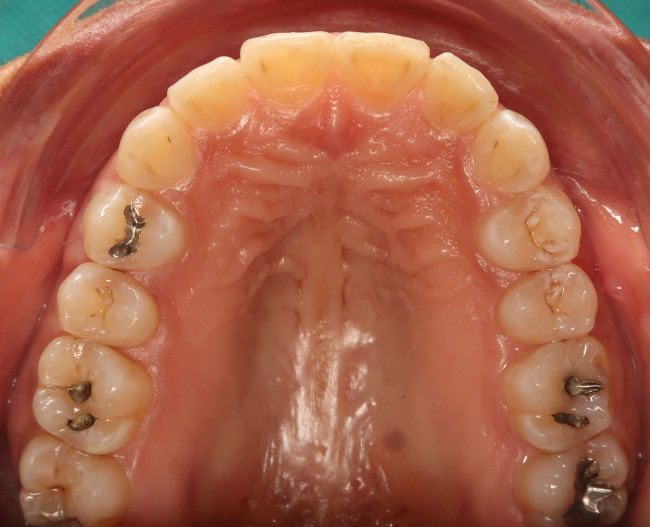

Der intraorale Befund (Abb. 2a–e) sowie die Modellanalyse (Abb. 3a–e) zeigten neben dem Diastema mediale im Oberkiefer vor allen Dingen eine Anteinklination und Supraokklusion beider Fronten. Besonders anterior wiesen beide Zahnbögen eine transversale Enge auf. Dies zeigte sich in einem deutlichen Unterkieferfrontengstand mit Labialkippung des Zahnes 41. Neben Abrasionen und Schlifffacetten, vor allem in der Front, waren auch vereinzelt Gingivarezessionen erkennbar. An Zahn 11 lag eine Schmelzfraktur der Inzisalkante vor. Durch die zwangsgeführte Laterognathie ergab sich eine Mittellinienverschiebung nach rechts von 3 mm. Eine beidseitige Distalokklusion bei vergrößerter sagittaler (6 mm) und vertikaler (5 mm) Stufe war erkennbar. Aufgrund der deutlichen transversalen Zahnbogenenge im Unterkiefer ergab sich links eine Tendenz zum Scherenbiss.